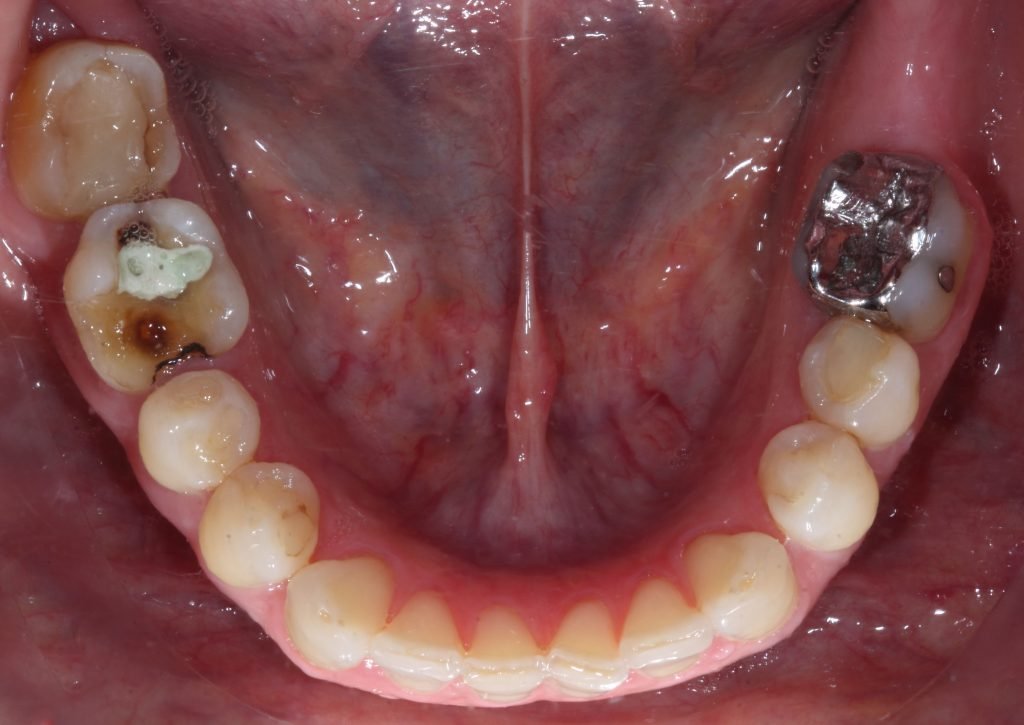

Punto Bajío Casos Clínicos Prótesis Fija sobre Implante unitario Inicio Provisional Final Prótesis Parcial Fija sobre 2 Implantes 2 Implantes Final Prótesis Bucal Removible Inicial Inicial Superior Inicial Inferior Rayos X Inicial Rayos X Inicial Frontal Final Final Superior Final Inferior Prótesis Parcial Fija/ Coronas de Circonio Sonrisa Inicial Foto Inicial Foto Inicial Inferior Foto Final Inferior Foto Final Sonrisa Final Prótesis Total Protesis Inmediatas 1 Protesis Inmediatas 2 Prótesis Removible/ Coronas Metal-Ceramica Carillas Incrustaciones Endodoncia